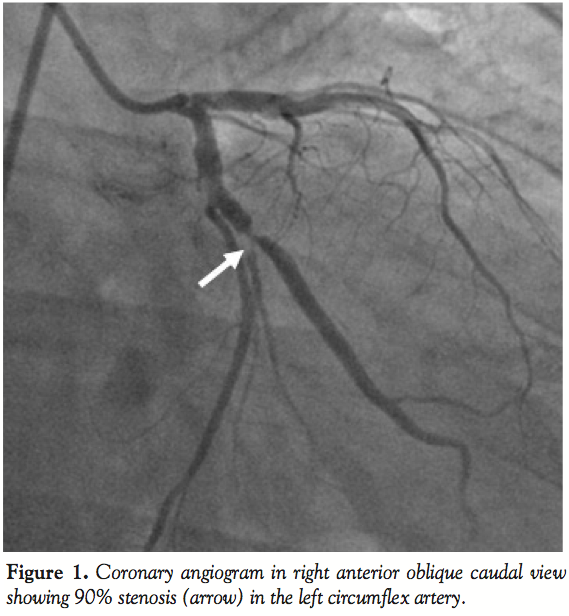

wire (Cordis Corporation, Miami Lakes, Florida) and predilated with a 2.5 x 10 mm Firestar balloon (Cordis Corporation). Residual stenosis was treated with a 3.5 x 13 mm Pronova drug-eluting stent (Vascular Concepts, Bangalore, India). Following stent deployment, incomplete expansion was noted in the mid-portion of the stent. A new 3.5 x 10 mm Firestar balloon (Cordis Corporation) was prepared and placed in the stented segment of the artery for in-stent dilatation. On attempting to inflate the balloon, we realized that the balloon was inflating predominantly in its distal portion (Figure 2). Thus, a negative suction was applied on the balloon catheter to deflate it. However, the distal portion of the balloon did not deflate. We tried to repeat the inflation and deflation of the balloon multiple times after diluting the contrast in the inflation device, but the balloon failed to deflate. Gentle traction was given on the shaft of the balloon while maintaining the negative suction, thinking that the partially inflated balloon might come out. While traction was applied, there was no movement of the balloon within the stent. Subsequently, the shaft of the balloon came out, while the partially inflated balloon was at its original position within the stent. This confirmed that the shaft of the balloon catheter had broken. The patient developed severe chest pain with ST-segment elevation along with hypotension. Angiogram revealed an occluded LCX starting at the inlet of the stent (Figure 3). The LAD also showed TIMI-2 flow. We quickly wired the LAD to maintain the access, anticipating a later thrombogenic complication in the same. An additional 2,500 U of unfractionated heparin were also given. The cardiac surgery team was alerted and surgical retrieval of the entrapped system was planned. In the meantime, a Whisper wire (Abbott Vascular International, BVBA, Belgium) was maneuvered through the stent with difficulty and positioned in the distal artery (Figure 4). Anticipating that a sufficient length of the shaft of broken balloon had been retained inside and was extending into the GC, a 2.5 x 9 mm Maverick balloon (Boston Scientific, Natick, Massachusetts) was advanced over the second wire and positioned near the tip of the GC and inflated to 14 atm so that the proximal part of the broken balloon shaft was trapped between the outer wall of the inflated balloon and inner wall of the GC. A gentle attempt to withdraw the assembly failed to show any movement of the assembly. The balloon was quickly withdrawn. A 2 x 9 mm Maverick balloon was negotiated with great difficulty through the stent on the second wire alongside the partially inflated broken balloon (Figure 4). The balloon was quickly inflated to 5 atm and withdrawn to position it just